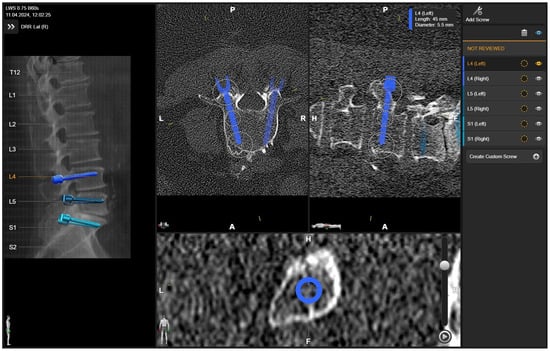

• Preoperative imaging and screw planning. In addition to magnetic resonance imaging (MRI) of the spinal region to be examined and instrumented, all patients received preoperative three-dimensional (3D) CT imaging of the part of the spine that was to be stabilized. The MRI and CT data were exported to the BrainLab navigation software (https://www.brainlab.com/surgery-products/overview-spinal-trauma-products/spinal-navigation/, accessed date 20 June 2025) and fused either rigidly or elastically. The navigation software includes a screw planning application that was used to plan the radius, length, and trajectory of the PS prior to surgery. The software enables automatic identification of the vertebra, followed by automatic screw planning for PSs in the selected vertebra. The proposed preplanned screws were then manually corrected according to the surgeon’s preference. For this step, it was crucial to have an artifact-free, high-resolution 3D CT of the spine, i.e., the area intended for instrumentation. (Figure 1 and Figure 2) [4].

Figure 1. Preoperative (A) anterior–posterior (AP) and (B) sagittal reconstruction of bone anatomy according to preoperative CT with automatic identification of vertebras. (C) Screw recommendations in selected vertebrae for stabilization of L4-S1.

Figure 2. Screw planning includes the entry point, trajectory, diameter, and length of the screw. The proposed screw plan can be modified manually according to the surgeon’s preference.